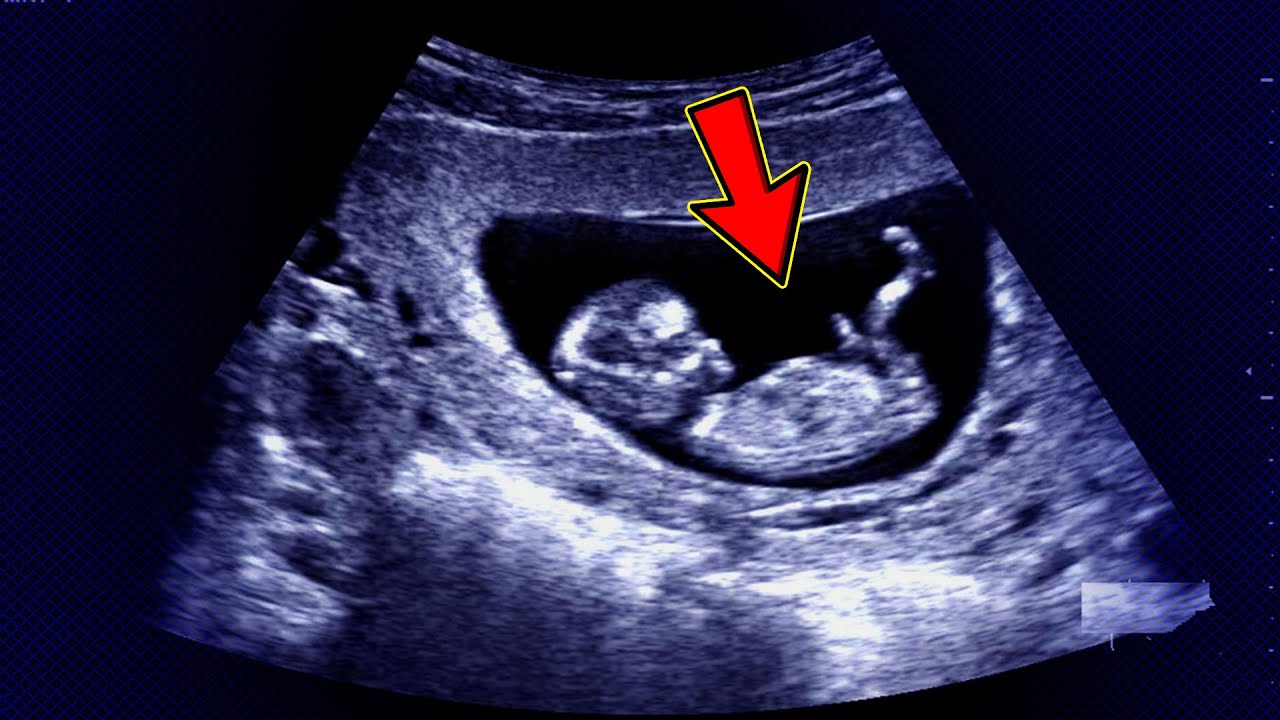

- الموجات فوق الصوتية: يتم وضع محول طاقة على بطن الأم وتعمل الموجات الصوتية على تكون صورة للجنين في أحشائها ويمكن قياس معدل نبضات القلب عن طريق النظر إلى صورة الموجات الفوق صوتية، وتُعد هذه الطريقة هي الطريقة الأكثر شيوعًا لمعرفة نبضات قلب الجنين.